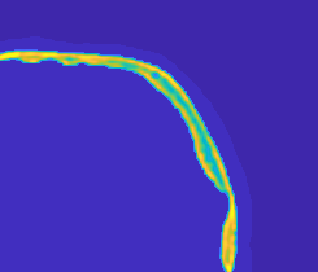

Model-based treatment planning for transcranial ultrasound therapy typically involves mapping the acoustic properties of the skull from an x-ray computed tomography (CT) image of the head. Here, three methods for generating pseudo-CT images from magnetic resonance (MR) images were compared as an alternative to CT. A convolutional neural network (U-Net) was trained on paired MR-CT images to generate pseudo-CT images from either T1-weighted or zero-echo time (ZTE) MR images (denoted tCT and zCT, respectively). A direct mapping from ZTE to pseudo-CT was also implemented (denoted cCT). When comparing the pseudo-CT and ground truth CT images for the test set, the mean absolute error was 133, 83, and 145 Hounsfield units (HU) across the whole head, and 398, 222, and 336 HU within the skull for the tCT, zCT, and cCT images, respectively. Ultrasound simulations were also performed using the generated pseudo-CT images and compared to simulations based on CT. An annular array transducer was used targeting the visual or motor cortex. The mean differences in the simulated focal pressure, focal position, and focal volume were 9.9%, 1.5 mm, and 15.1% for simulations based on the tCT images, 5.7%, 0.6 mm, and 5.7% for the zCT, and 6.7%, 0.9 mm, and 12.1% for the cCT. The improved results for images mapped from ZTE highlight the advantage of using imaging sequences which improve contrast of the skull bone. Overall, these results demonstrate that acoustic simulations based on MR images can give comparable accuracy to those based on CT.